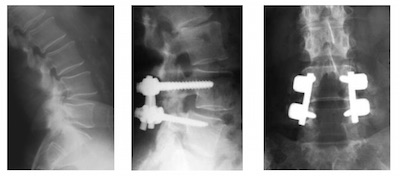

• Une fois effectuée la libération des éléments nerveux, il est nécessaire de fusionner ("souder") les vertèbres du spondylolisthesis. Ce geste, en langage chirurgical, est dénommé arthrodèse. En pratique, des vis sont isérées dans la vertèbre du haut, et dans la vertèbre du bas. Ces vis sont connectées par des tiges. L'os qui a été retiré lors du temps de laminectomie est alors repositionné entre les parties arrière des vertèbres pour réaliser une greffe osseuse et permettre ainsi une consolidation durable du montage. (on parle de greffe postero-latérale

• Parfois, on peut compléter durant la mêm intervention cette greffe postérieure par une greffe antérieure dans l'epace discal. On parle alors de greffe "intersomatique". Cette greffe est maintenue en place par un petit boitier que l'on appelle une "cage"

spondylolisthesis dégénratif

Spondylolisthesis L4L5- Vue pré et postopératoire avec le matériel